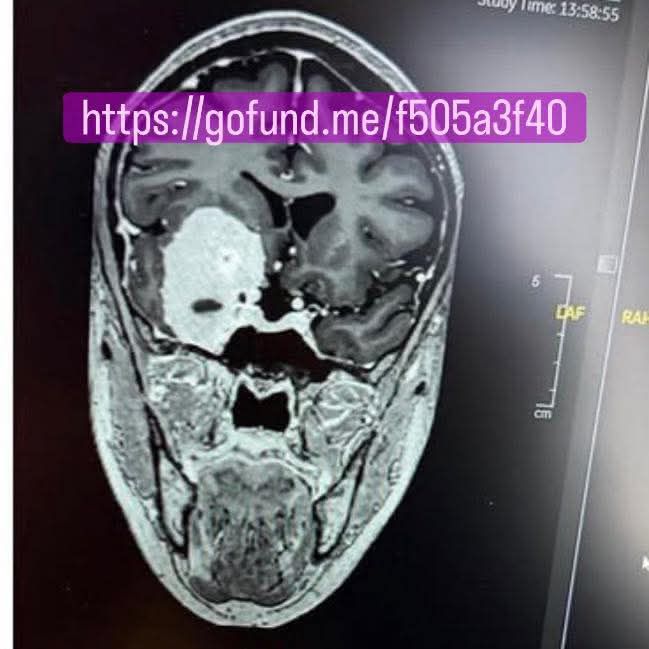

While sitting down to post my blog, though, I saw a post which made me cry. A friend who I met 26.5 years ago on our first day of our new job at Norwich Union (now Aviva) had a date for her surgery to remove a brain tumour. About 15 years ago she met her now husband and later moved to the States to be with him. I remember this as it was around the same time I met Captain Caveman and we would both end up moving abroad ‘for love’. I’m older than her and have probably abused my body and made worse lifestyle choices than she has, so there’s something that happened to put so much in to perspective today. I didn’t even need a Gratitude List today, as it would just read ‘everything’. Over the years we’d not kept in touch as much and I’d never met her American hubby. I messaged her and we had a conversation about how she was feeling, she was being brave and was understandably shitting herself. I shared her go fund me page on my Facebook and I got a message from another friend to ask if I’d been hacked. I imagine, like me she also thought it might be too unbelievable to be true. It wasn’t!

If you’re reading this and are able to donate towards Angela’s medical costs, it would be much appreciated. Here’s a link and her photo of what the tumor looks like.

https://gofund.me/61f18c7b3